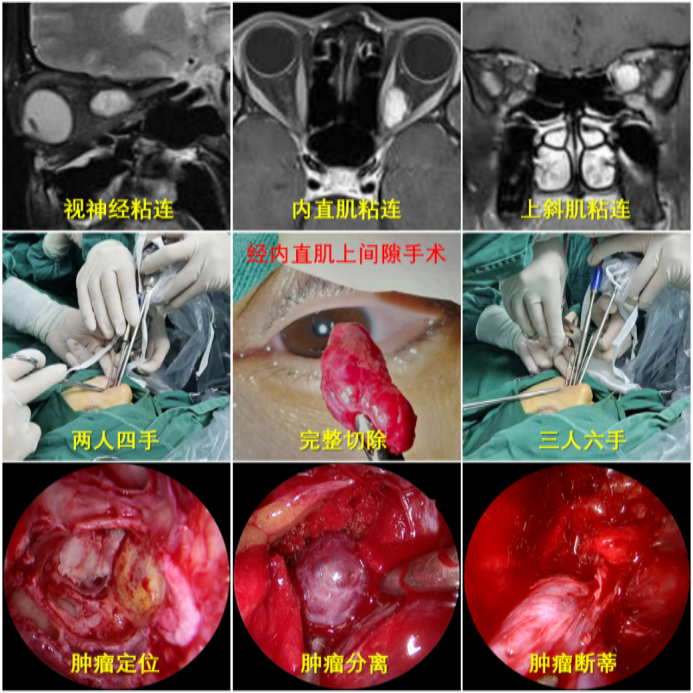

多年来,贵州航天医院各科室紧跟医学前沿,不断强技术、补短板,大力开展新技术、新项目,完成了许多高精尖、高难度、本地区“首例”的技术,填补了医院医疗技术空白,满足了群众日益增长的医疗需求。 案例分享 患者在两年前无明显诱因出现左眼胀痛、左眼视力下降等症状,由于当时患者自感不太严重,未予重视,随着时间的推移,症状逐渐加重,遂前来我院就诊,为更好的为患者进行诊治,收入了耳鼻喉科。经眼科查体显示:VOD(矫正视力)→1.0,VOS(矫正视力)→1.0,进行眼眶平扫+MRI检查后,初步诊断为:左眼球后脂肪间隙内占位,考虑良性病变,血管瘤可能。 考虑到患者病情复杂,耳鼻喉科组织眼科、麻醉科等科室开展了多学科联合会诊,对患者病情、既往病史等进行了全面深入的综合分析研讨,制定了鼻内镜下左侧鼻窦功能开放术+左侧眶内肿瘤切除术的方案,由于手术难度较大,在充分告知手术风险及并发症等相关信息后,患者及家属同意手术。经过充分的术前准备,耳鼻喉科借助经鼻内镜,成功通过鼻窦经由筛窦眶纸板、蝶窦外侧壁将肿瘤完整切除,最大程度地保护了眶内的血管、神经等重要组织。 术后,患者未出现视力减退、视野缺损等并发症,仅眶周稍青紫肿胀和轻微复视。患者2周后复查,复视症状、眶周青紫肿胀消除,术后MRI(眼眶平扫+增强扫描)显示左眶内肿物已消失。 该技术的开展,特别邀请了中山大学附属第一医院耳鼻喉科专家左可军教授莅临主刀,并对该技术的实施进行指导,已成功完成多例鼻眼相关内镜手术,解决了患者外出就医难、排队时间长、花费多等难题,让广大民众在家门口享受到了优质的医疗服务资源。 什么是鼻内镜下经鼻腔、 鼻窦进路眶内肿物切除术 眼眶是一个狭小的解剖间隙,结构复杂,功能重要,周围临近组织较多,含有许多重要结构,眶深部的肿瘤切除手术难度大,容易侵犯神经,出现视力丧失等并发症。随着眼-鼻相关学科发展和微创理念的深入,鼻内镜内侧开眶入路得到显著发展和应用,鼻内镜下经鼻腔、鼻窦进路眶内肿物切除术,具有微创、直视、并发症少等优势,目前已成为眶内肿物切除首选手术进路,主要应用于泪道系统疾病、眶骨折修复、眼眶内侧肿瘤切除、眼眶减压、海绵状血管瘤切除等。 鼻内镜下经鼻腔、鼻窦 进路眶内肿物切除术原理 手术基于先进的鼻内镜设备,通过鼻腔入路直接对眼眶及其毗邻区域进行操作,鼻腔与眼眶相邻,眼眶内侧壁主要由筛骨纸板构成,骨质菲薄,很容易经此进入眼眶,所以鼻腔可作为合适的手术通道,让操作更精准、更微创,同时,内镜下经鼻眼眶手术可利用该通道实现面部无切口。 鼻内镜下经鼻腔、鼻窦 进路眶内肿物切除术优势 ✔肿物可完整切除,较好的保护视力。 ✔可避免眼外部入路及经颅开眶入路的头面部切口。 ✔无脑组织的牵拉损伤,对眼内容物的牵拉损伤较小。 ✔经鼻切口外形无改变,术中组织结构放大、视野清晰,肿物分离更便捷。 贵州航天医院耳鼻喉科专家团队 左可军 中山大学 附属第一医院耳鼻咽喉科 贵州航天医院耳鼻喉科 特聘教授 医学博士 硕导 主任医师 临床擅长:鼻科、鼻眼相关外科、鼻颅底相关外科以及鼻变态反应科的临床和基础工作。 南方青年鼻科联盟创始人,担任中国医师协会耳鼻咽喉科分会整形美容学组委员、海峡两岸医药卫生交流协会眼科学专业委员会眼科内窥镜微创手术学组委员、广东省精准医学应用学会头颈肿瘤分会副主委、广东省中西医结合学会耳鼻咽喉科分会副主委、广东省眼健康协会眼与全身疾病专业委员会常委。获得国家二级运动员和南粤优秀研究生称号,2018年荣获“广东医院最强科室之实力中青年医生”,2020年荣获全国卫生健康系统抗疫先进集体、中国医师协会耳鼻咽喉头颈外科分会抗疫先进个人,2021年荣获广东省科技进步一等奖,2023年荣获第七届“羊城好医师”。 张光进 耳鼻喉科主任 副主任医师 临床擅长:对耳鼻喉头颈常见病的诊治具有丰富的临床经验,擅长鼻内镜、耳内镜、耳显微、头颈咽喉部肿瘤及眩晕手法复位等的诊疗。 曾先后前往第三军医大学西南医院、复旦大学耳鼻喉科医院、上海新华医院及北京友谊医院进修学习;遵义市医学会常务委员;主持及参与级科研课题2项,发表专业论文10余篇。 陈维信 耳鼻喉科 主任医师 临床擅长:对耳鼻喉科常见疾病的诊治具有丰富的临床经验,擅长耳、鼻、喉及头颈部位的手术。 曾先后前往上海交通大学附属仁济医院耳鼻喉-头颈外科、北京大学人民医院耳鼻喉-头颈外科参加鼻内镜外科进修学习。中国睡眠研究会委员,贵州省医学会耳鼻喉-头颈外科学分会委员,贵州省耳鼻喉-头颈外科学会理事,贵州省医学会变态反应学分会委员,贵州省防聋治聋技术指导组专家,遵义市耳鼻喉科分会副主任委员,遵义市医疗事故鉴定专家库成员;主持省部级科研课题2项,发表专业论文20余篇。 秦 晋 耳鼻喉科 副主任医师 临床擅长:对耳鼻喉科常见疾病的诊治具有丰富的临床经验,擅长耳、鼻、喉及头颈部位的手术。 遵义市医学会常务委员;曾先后在第三军医大学西南医院、湖南湘雅鼻颅底培训班进修学习。 贵州航天医院耳鼻喉科简介 基本情况 贵州航天医院耳鼻喉科拥有一支经验丰富、技术精湛的医疗团队,共有医师9名,其中副高级以上专家5名,医学硕士2名,开放床位20张,拥有德国WOLF鼻窦内窥镜系统、日本奥林巴斯电子喉镜、奥林巴斯电子鼻咽镜、丹麦临床听力监测设备、声导抗仪、听觉诱发电位、耳声发射仪、美国杰西低温等离子治疗仪、杭州好克鼻窦内窥镜系统、鼻动力系统、耳显微镜、耳用电钻、微波治疗仪等先进设备。 专科特色 (一)耳部疾病 耳内镜下胆脂瘤切除术、III型鼓室成形术+人工听骨听骨链重建术。 (二)鼻部疾病 内镜下鼻息肉切除术、鼻窦功能开放术。 (三)咽喉疾病 内镜下扁桃体、腺样体低温等离子切除术。 (四)交叉学科 1.经鼻内镜下眶内肿瘤切除术 2.经鼻内镜下鼻腔泪囊吻合术 诊疗范围 (一)常见耳疾的诊断和治疗:中耳炎、耳聋、耳鸣等。通过各种耳科检查手段,如耳镜检查、听力测试和耳脑干听觉诱发电位检查等,准确诊断患者病情,制定个性化治疗方案。 (二)鼻炎、鼻窦炎、鼻出血等鼻科疾病的诊断和治疗:采用微创技术,如鼻内窥镜检查、低温等离子手术等,为患者提供有效的治疗方案。 (三)喉炎、声带息肉、声带白斑等喉科疾病的诊断和治疗:通过声带电子镜、喉镜等设备,准确判断患者的喉部病变,为患者提供精准的治疗方案。 (四)鼻眼、鼻颅底相关手术。